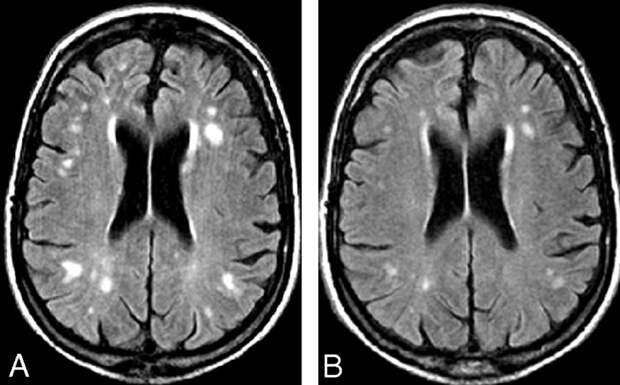

По характеру первопричины патологии делят на диффузные и очаговые […] The post Очаговые поражения головного мозга: виды, причины, симптомы, диагностика и лечение first appeared on Информационное Агентство 365 дней.